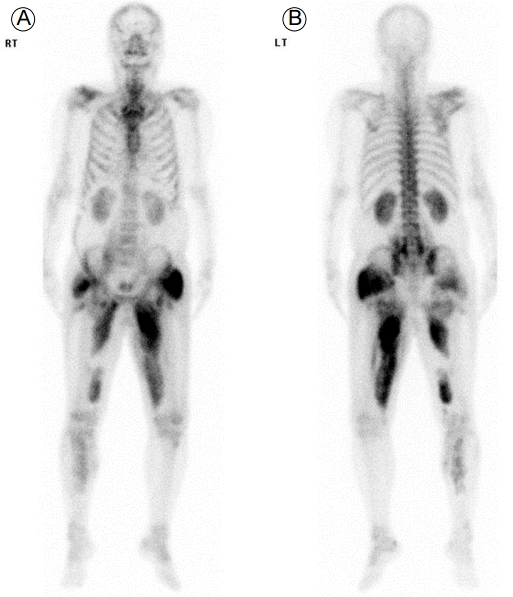

환 자: 51세 남자주 소: 의식 혼미현병력: 특이 병력이 없는 환자로 수면 장애로 졸피뎀을 처방받고 간헐적으로 복용 중이었다. 내원 6시간 전으로 추정되는 자살을 목적으로 모아둔 졸피뎀 1,200 mg (120정)을 집에서 복용한 후 계속적인 강한 외부 자극에 의해서만 깨어나는 의식 혼미가 보여서 응급실로 내원하였다. 외상은 관찰되지 않았으며 알코올 섭취 유무는 확인할 수 없었다.과거력: 고혈압 진단을 받았으나 치료받지 않고 지냈다.사회력: 특이사항은 없었다.가족력: 특이사항은 없었다.진찰 소견: 입원 당시 혈압 120/70 mmHg, 맥박수 118회/분, 호흡수 24회/분, 체온 36.5°C였다. 의식은 명료하지 않았으며 급성 병색을 보였다. 두경부 검사에서 경정맥 울혈은 보이지 않았다. 흉부 청진상 심음은 규칙적이었고, 심잡음이나 수포음은 청진되지 않았다. 복부팽만도 보이지 않았다. 피부 긴장도는 정상을 보였으며 하지 부종은 없었다. 양쪽 상하지 근력 저하는 보이지 않았고 감각 기능이나 심 부건 반사는 정상적으로 좌우 대칭이었다.검사 소견: 입원 당시 시행한 말초 혈액 검사에서 백혈구 25,400/mm3 (중성구 78.6%), 혈색소 16.0 g/dL, 혈소판 227,000/mm3, 적혈구 침강 속도 41 mm/h, C-반응성단백 35.5 mg/dL였다. 혈청 생화학 검사에서 혈청요소질소(blood urea nitrogen, BUN) 12.9 mg/dL, 크레아티닌(creatinine, Cr) 2.5 mg/dL, 아스파르테이트 아미노 전달효소/알라닌 아미노 전달효소 74/25 IU/L, 나트륨/칼륨/클로라이드/총 이산화탄소량 143/5.4/97/11 mEq/L, 칼슘 8.6 mg/dL, 인 8.9 mg/dL, 요산 12.6 mg/dL, 젖산탈수소효소 2,913 IU/L, 크레아틴 인산활성효소(creatine phosphokinase, CPK) 3,909 IU/L, 미오글로빈 > 10,000 ng/mL로 측정되었다. 동맥혈 가스 검사에서 pH 7.391, pCO2 28.8 mmHg, pO2 82.2 mmHg, HCO3- 17.1 mmol/L, SaO2 96.2%였다. 단순 요 검사에서 산도 5.4, 비중 1.030, 알부민 trace, 잠혈 1+, 백혈구 0-1/HPF, 적혈구 0-1/HPF 소견을 보였다. 그 외 VDRL, HBs Ag, anti-HCV Ab 및 anti-HIV Ab 검사는 모두 음성이었다.방사선 소견: 흉부 X-선 촬영에서 양측 폐 음영은 정상이었고, 심장비대는 보이지 않았다. 99mTc-MDP 전신 골 스캔상 우측 어깨 관절, 상박부, 복부, 양측 골반, 허벅지 및 종아리 연부조직에서 방사성 동위원소의 미만성 섭취 증강 소견이 관찰되었다(Fig. 1).치료 및 경과: 응급실 내원 직후 신기능(Cr 2.5 mg/dL) 및 CPK, 미오글로빈의 상승 소견과 99mTc-MDP 전신 골스캔상 여러 부위의 연부조직에서 방사성 동위원소의 섭취 증강 소견이 보여 횡문근융해증으로 인한 급성 신손상으로 진단하였다. 원인 약제인 졸피뎀 중단과 함께 대량의 수액 요법과 적절한 요량 유지를 위해서 이뇨제 라식스(furosemide)를 병용 투여하였다. 입원 2일째 횡문근융해증 치료를 위해 4,000 mL/day 이상 대량의 수액 치료와 함께 라식스 20 mg/hr로 지속적인 정맥 주입을 하였으나 요량 1,000 mL/day 정도로 충분한 요량이 얻어지지 않으면서 호흡곤란 증상과 함께 폐 부종을 포함한 전신 부종이 관찰되었다. BUN 59.9 mg/dL, Cr 5.8 mg/dL (acute kidney injury network stage 3), CPK 16,210 IU/L, 미오글로빈 > 10,000 ng/mL로 상승하여 경정맥 이중 내강 도관 삽입 후 응급 고유량 혈액투석을 시행하였다. 입원 7일째 3,000 mL/day 이상의 요량 증가를 보이면서 폐 부종을 포함한 전신 부종의 호전과 함께 의식 수준은 청명하여 혈액투석 4회 시행 후 중지하였다. 수액 요법 등 보존적 치료는 지속하면서 경과를 관찰하였다. 입원 1달째 BUN/Cr 16.6/1.0 mg/dL, CPK 95.2 IU/L, 미오글로빈 80.5 ng/mL로 급성 신손상 및 횡문근융해증의 호전과 함께 증상의 호소 없이 안정적으로 유지되었다(Fig. 2).

Figure 1.

Full-body bone scintigraphy with 99mTc-methylene diphosphonate performed on the 6th hospital day revealed diffusely increased isotope uptake in the soft tissues of the right shoulder and upper arm, abdomen, and both hips, thighs, and calves. RT, right; LT, left.